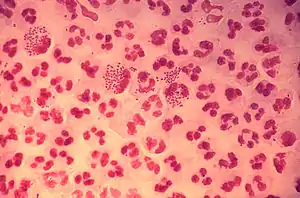

Гоноре́я (англ. gonorrhea, лат. gonorrhoea; у розмовній мові також трипер[9], заст. чєрвєница[10], наконе́шник[11]) — венерична інфекційна хвороба, яка перебігає із запаленням сечостатевих органів людини. Хворобу спричинює гонокок, якого виявив Альберт Нейссер. Гонорею відносять до найпоширеніших бактеріальних інфекцій: за даними ВООЗ щорічно у світі захворює не менше 150—180 млн людей.

На слизовій оболонці статевих органів збудник гонореї — гонокок — посилено розмножується, спричинює її запалення, яке йде з набряком і сильним виділенням гною. Ушкоджені місця слизової оболонки починають дуже різати і пекти, на них виникають ерозії. Хвороба ускладнюється порушенням відтікання сечі. У крові гонокок швидко гине, тому на відміну від сифілісу, гонорейна інфекція часто має місцевий характер. В ослаблених людей із зниженим імунітетом гонокок може поширюватись по всьому організму, уражаючи суглоби, серцевий м'яз, навколосерцеву сумку. Гонокок виділяє токсин, і через це, крім місцевих уражень, у такого хворого спостерігається слабкість, втрата апетиту, головний біль.